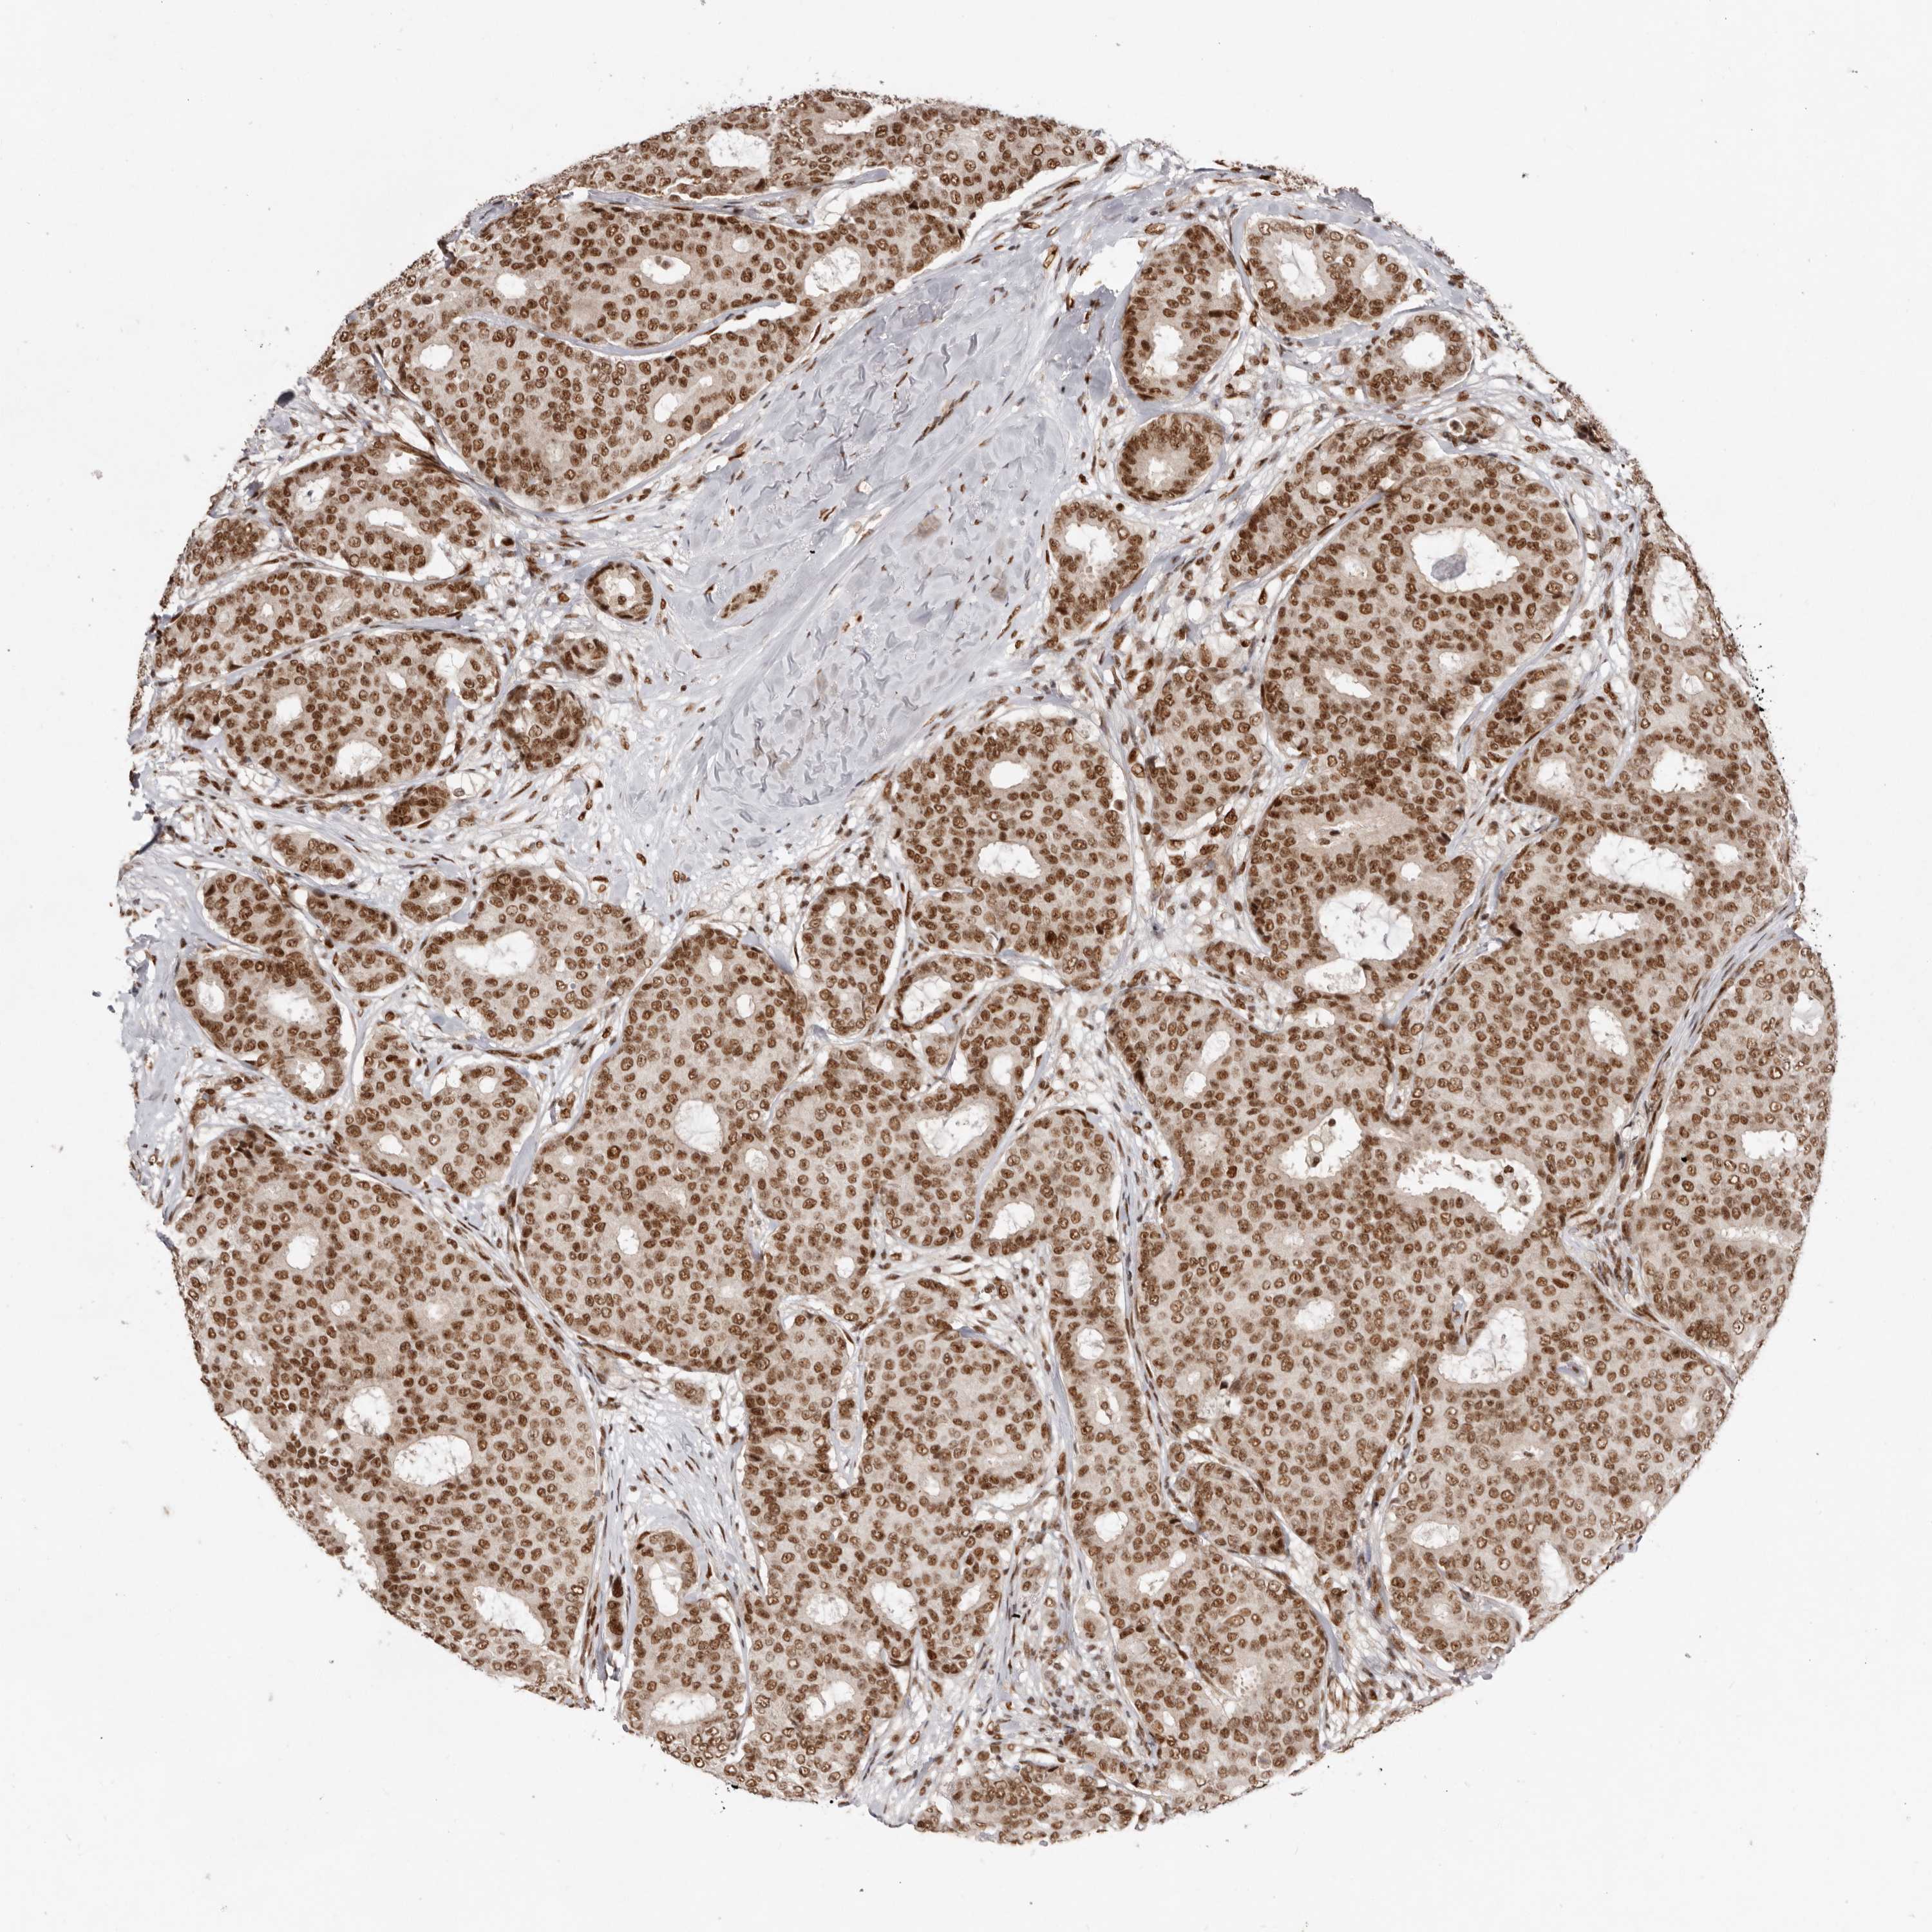

CANCER BREAST CANCER Show tissue menu

BRCA TCGA BRCA VALIDATION PROTEIN EXPRESSION